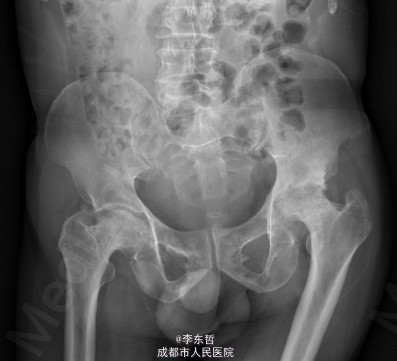

患者男,62岁,因“双髋疼痛4年,加重伴活动受限1年”入院。病员诉入院前4年无明显诱因出现双侧髋部疼痛,行走后疼痛加重,疼痛能忍受,双侧髋部无红肿,皮温不高,无畏寒、发热,休息后疼痛能自行缓解,无夜间疼痛,在当地医院行止痛药内服、理疗治疗,疼痛稍缓解。逐渐加重,1年前双侧髋部疼痛、跛行明显加重,左髋活动受限,行走困难,给予对症治疗症状无明显改善,遂到我科门诊就诊,X线片提示:双侧股骨头坏死,建议手术治疗,故于今日以“双侧侧股骨头坏死”收入我科进一步治疗。

查体:生命体征平稳,心肺腹未见异常;跛行,双左下肢较右下肢短缩1cm,左、右腹股沟中点深压痛,左、右髋叩击痛,左髋屈20°,伸0°,外展10°,内收10°,右髋屈60°,伸0°,外展20°,内收20°。双髋内、外旋活动受限,诱发疼痛,左侧重。 辅助检查:x线片示双侧股骨头坏死、塌陷变形,左侧明显,左髋半脱位。

初步诊断:1、左侧股骨头坏死伴内收肌挛缩(Ficat IV期);2、右侧股骨头坏死(Ficat IV期);3、右膝骨关节炎伴外翻畸形;入院后积极完善术前检查及准备,择期行手术治疗。